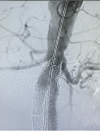

Figure 7

Figure 7. Control aortography showing proximal segment of the endoprosthesis free from leaks and stents correctly positioned in the renal arteries.